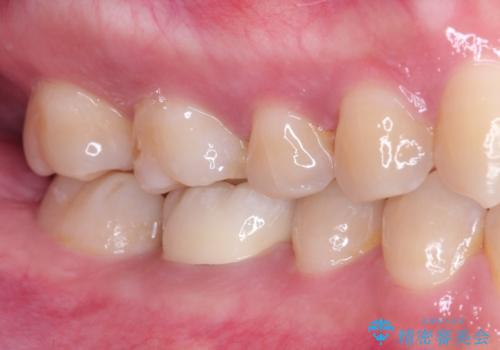

奥歯が痛い。根管治療~オールセラミッククラウン

- 奥歯の痛みを主訴に来院されました。

検査の結果、神経は保存不可能と診断されたため、根管治療~オールセラミッククラウンによる治療を行いました。